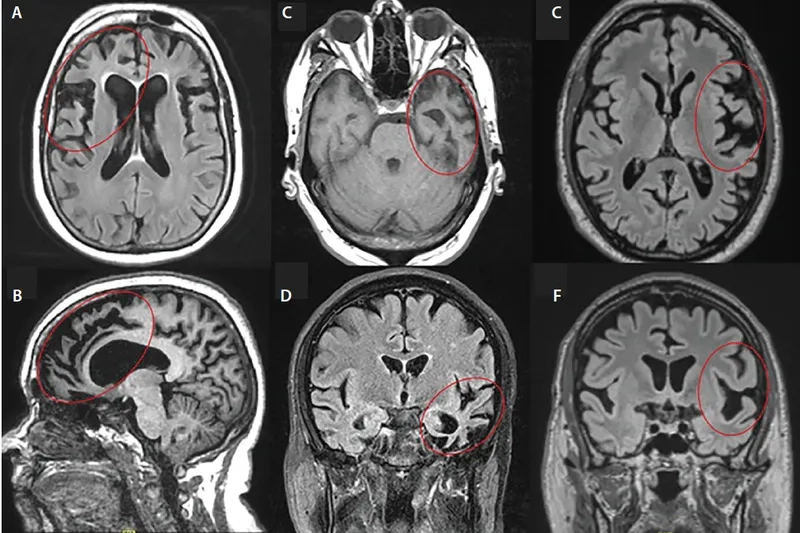

The most searched for Frontotemporal Dementia images

Understanding the behavioral frontotemporal dementia symptoms